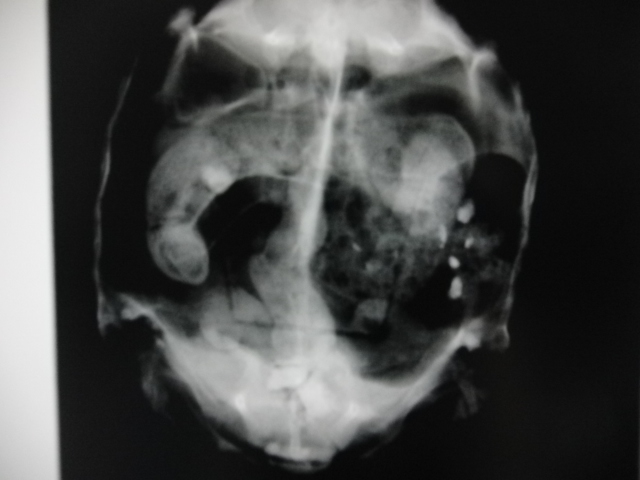

下のレントゲン写真の子は、膀胱内と総排泄腔に結石を認めました。

膀胱内に結石があるうちにはほとんど症状を示すことはありませんが、

膀胱から出て骨盤腔内や総排泄腔などで詰まってしまうと、

排尿困難や排便困難などを引き起こし、激しいいきみなどの症状を表します。

そうなると全身麻酔下での摘出を行う必要があります。